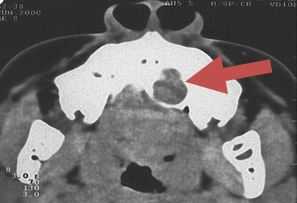

CLINICAL PRESENTATION C T SCAN EXAMINATION

Pleomorphic Adenoma of hard Palate